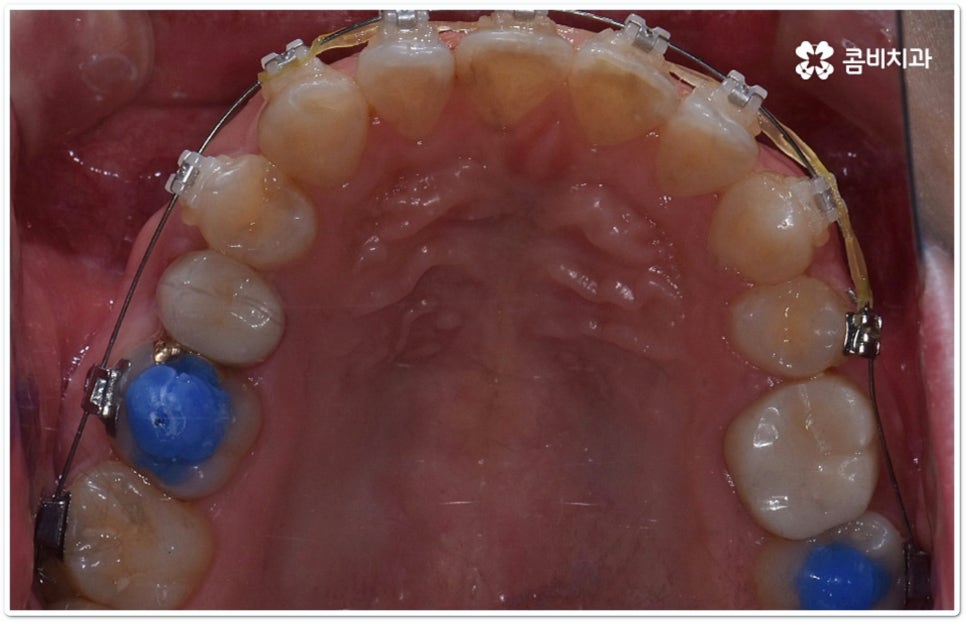

클리피씨교정 장치란 clippy-c 라는 단어 뜻에서 알 수 있듯이 클립이 달린 (clippy) 세라믹(ceramic) 브라켓 장치를 의미하고 있어요. 예전에 교정 장치에서 많이 쓰이던 방식은 고무줄 또는 미세철사를 이용하여 브라켓마다 각각 와이어를 묶어주는 것으로 날카롭게 잘린 철사 끝부분에 자칫 상처를 입을 수도 있고 한 달에 한 번 정도 치과에 내원하여 진행 상황에 따라 교정력을 조정하는 시간도 훨씬 더 많이 걸렸다고 할 수 있습니다.

이와는 다르게 클리피씨교정 장치는 자가결찰방식이라고 해서 각 브라켓에 여닫을 수 있는 특수한 클립(뚜껑)이 달려 있어 전체 와이어를 통과시켜 잡아주는 방식을 이용하기 때문에 겉면이 매끄럽고 진료 시간도 짧아지며 마찰로 빠져나가는 교정력을 줄여주어 좀 더 효율적으로 치아를 이동시킨다고 할 수 있어요. 즉 보다 적은 힘으로 지속적이고 부드러운 치아 이동을 가능하게 하므로 언급했던 것처럼 개인차가 있지만 전체 기간을 약 6개월 정도 단축시키고 치아가 이동할 때 느낄 수 있는 초기 통증도 감소시켜 줄 수 있는 거예요. 또한 치아 색상과 비슷한 세라믹 재질을 이용하기 때문에 음식을 먹거나 대화를 하는 등 입을 벌렸을 때 보일 수 있는 교정 장치가 그렇게 크게 눈에 띄지 않아 심미적으로도 뛰어나다는 장점을 가지고 있습니다.